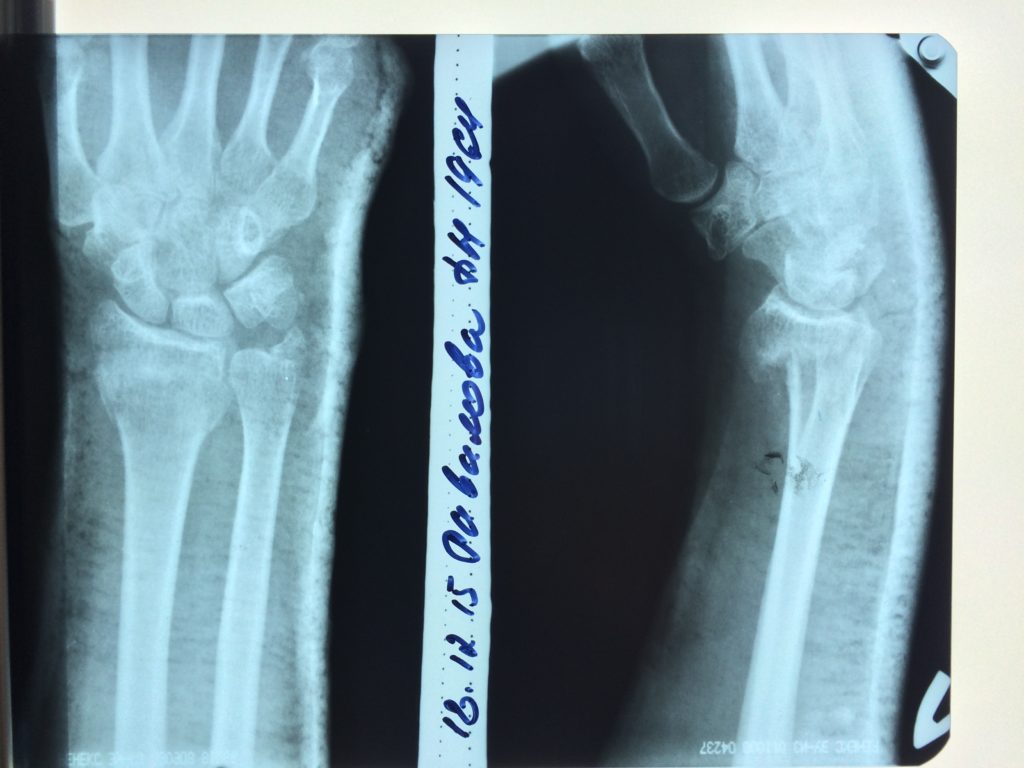

Использование материала Остеоматрикс при полифокальном внутрисуставном импрессионном переломе дистального эпиметафиза лучевой кости

Использование материала Остеоматрикс при полифокальном внутрисуставном импрессионном переломе дистального эпиметафиза лучевой кости.

Операция - открытая репозиция, остеосинтез лучевой кости пластиной с костной ксенопластикой материалом "Остеоматрикс". На контрольных снимках в три месяца имеется консолидация перелома, миграции фиксатора нет, имеется остеоинтеграция ксенопластического материала.